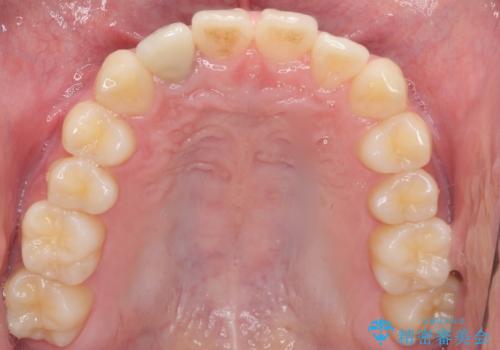

土台を白いファイバーコアにやりかえたのち、土台の色を透過させないジルコニアフレームを用いたセラミッククラウンによる治療を行いました。

自然な仕上がりにご満足頂けました。

治療終了時には「修正や仮付けをしてもらえて納得のいく治療を受けられました。この病院にして良かったです!」とおっしゃって下さいました。

クラウンの種類:オールセラミッククラウン スペシャル